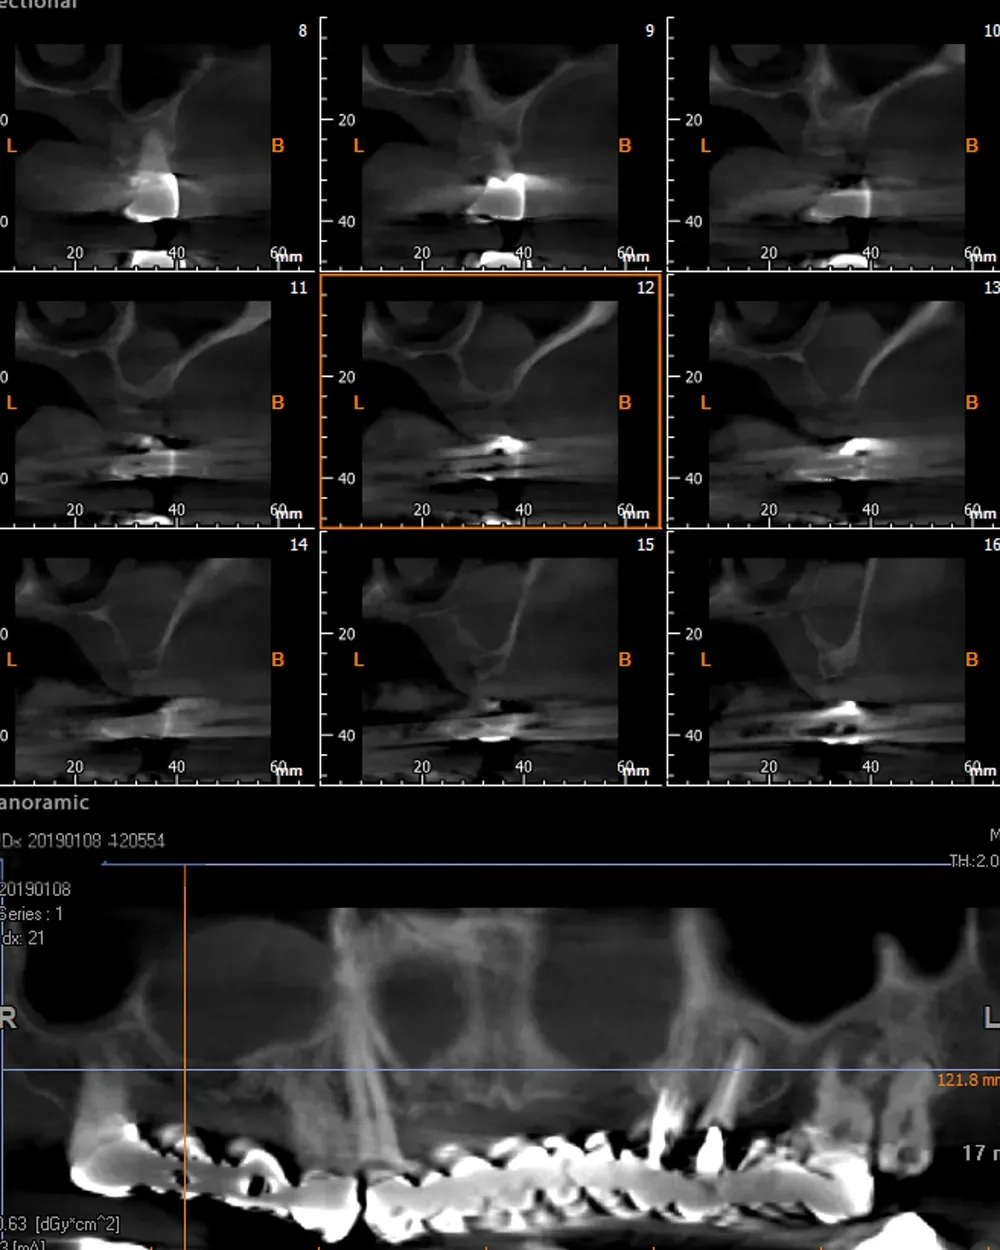

Le immagini sottostanti illustrano la situazione ossea pre-operatoria della cresta alveolare, con una grave atrofia orizzontale, corrispondente alla categoria H3 della Classificazione di Colonia (CCARD).

Secondo la BDIZ EDI, tale grado di atrofia controindica le tecniche espansive.

Personalmente, tuttavia, ritengo che con gli strumenti moderni sia possibile e consigliabile spingersi oltre per includere anche tale livello di atrofia tra le indicazioni. E questo caso lo dimostra.

Sul lato sinistro, l’atrofia dopo la rimozione dei denti e la rigenerazione era comunque meno grave e rientrava nell’ambito delle categorie S1-S2 CCARD. La prossima immagine è la CBCT della zona mascellare sinistra prima delle estrazioni.